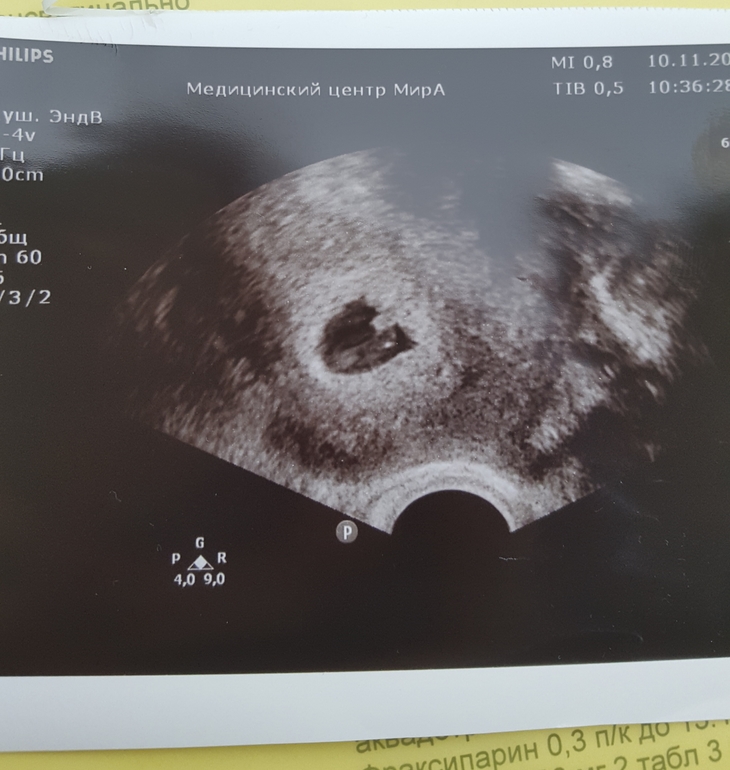

Наше узи!

Я БЕРЕМЕННА !Девочки, ура! Эмбрион 4.6 мм, сердцебиение чёткое и ясное!

Сердечко послушать не дали, но показали пульсацию.